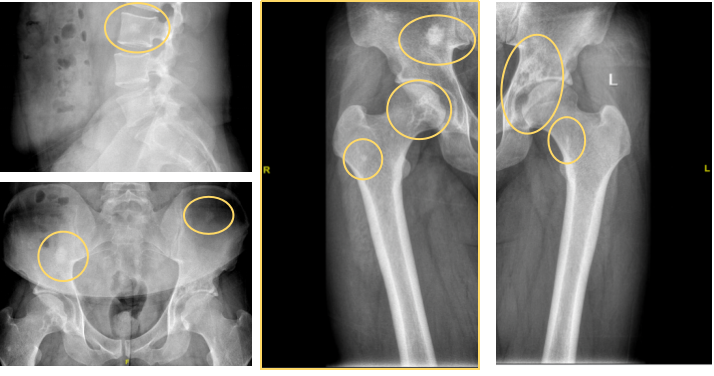

• 全脊柱+四肢长骨X线:约L3椎体重叠区高密度影;双侧髂骨结节状致密灶;左侧髋臼及右侧股骨头混杂密度灶,双侧股骨近段点状高密度灶(图2)。

图片2.png

图2 骨X线示中轴骨、四肢长骨近端多发高密度影